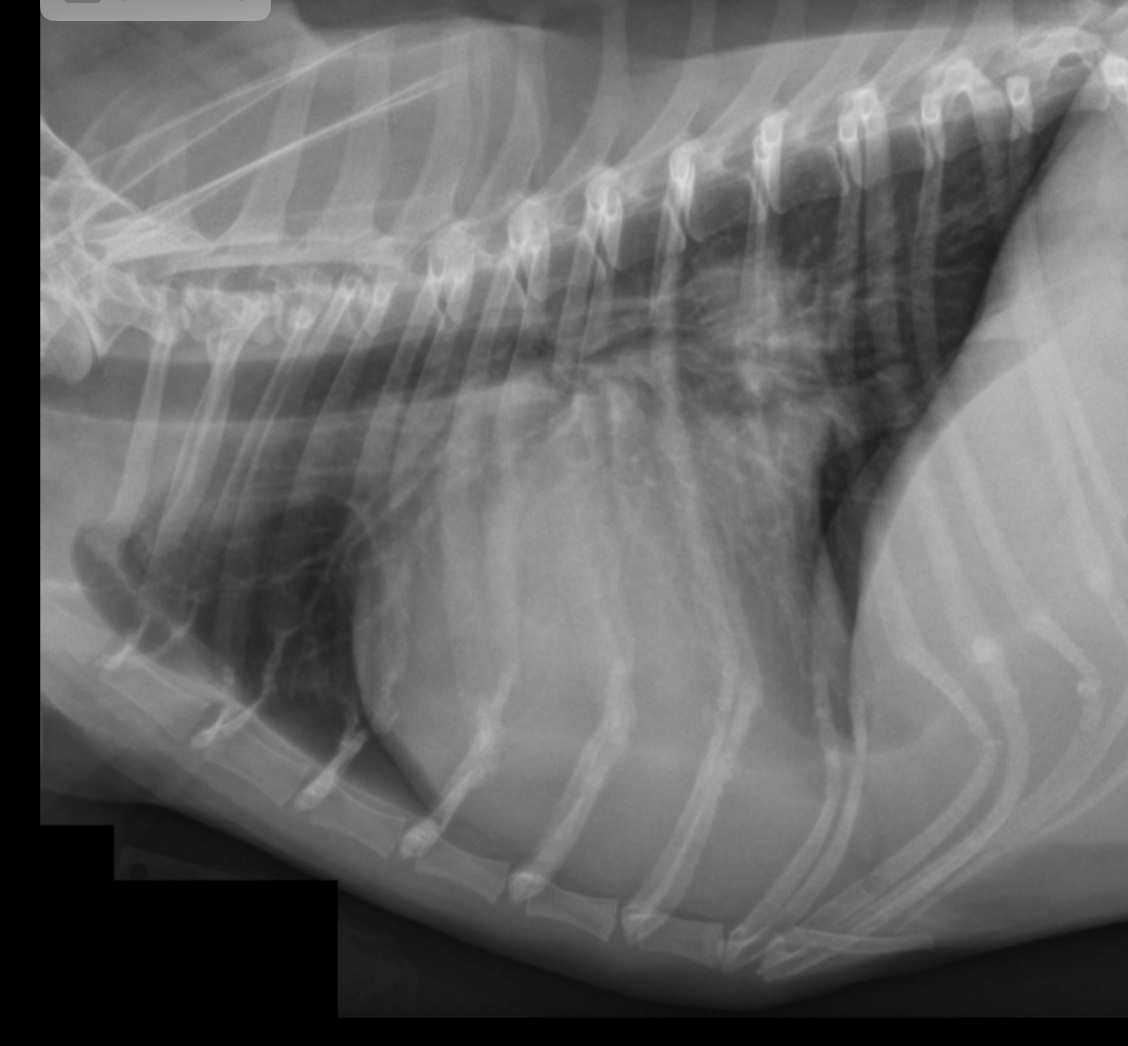

3 features LVE on lateral

-tall heart (>2/3 DV diameter)

-dorsal displacement of trachea (almost parallel to spine)

-straightening of cd. border of heart

What part of the heart is enlarged?

LVE (technically LAE too) - prof used the same photo for both but outlined different features